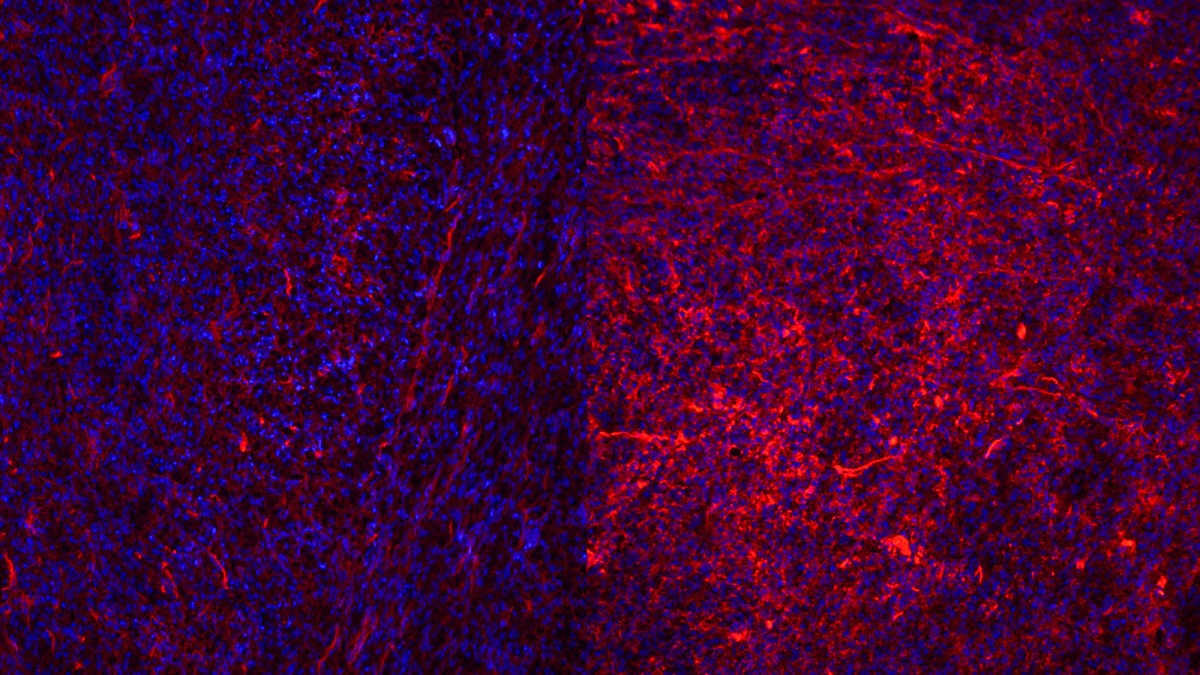

In microscope images of the extracellular matrix and cells, cells are stained in blue and collagen in red. Regressing tumors on the left are surround by less dense collagen compared to resistant ones (right) with dense collagen.

The ECM caught the team’s attention because researchers noticed striking changes in collagen, the matrix’s main structural protein, during treatment: The ECM becomes unusually dense and overproduced. “What we wanted to know is whether the changes in the ECM were just a side effect of therapy, or if they actually contributed to drug resistance,” said Dr. Chia-Hsin Hsu, doctoral student and first author of the study.

The team made two discoveries. First, they explained why even the most powerful targeted therapeutics can fail: They showed that the thickened matrix acts like a physical barrier, preventing cytotoxic T cells, the immune cells that directly kill cancer, from reaching the tumor.

“It was thrilling to see how changing the extracellular matrix could completely reshape the immune landscape of a tumor,” Hsu said. “Under the microscope, we could literally see cytotoxic T cells spreading more evenly once the ECM was reduced. It felt like uncovering a hidden mechanism that had been holding back the immune system from doing its job.”